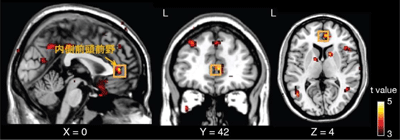

画像はリリースより

今回の研究では、ヒト臨床試験と動物実験のそれぞれで、オキシトシンの単回投与と反復投与による生化学的な変化の違いを調べた。ヒト臨床試験では、オキシトシン6週間経鼻投与の前後で、向精神薬を服薬していないASD当事者の内側前頭前野の代謝物濃度をプロトン磁気共鳴スペクトロスコピーで測定。その結果、6週間反復投与によって内側前頭前野のNアセチルアスパラギン酸濃度とグルタミン酸-グルタミン濃度和が有意に減少していた。このような代謝物濃度の減少は、単回投与では認められなかったものだという。また、この代謝物濃度の減少が目立つASD患者では、表情や声色に基づいて相手の友好性を理解している際の、内側前頭前野活動のオキシトシン投与による改善が少ない傾向を認めたが、このような相関関係はプラセボ投与では生じなかったとしている。